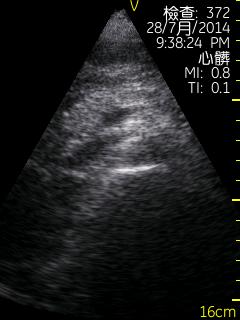

Vscan临床图片 腹部